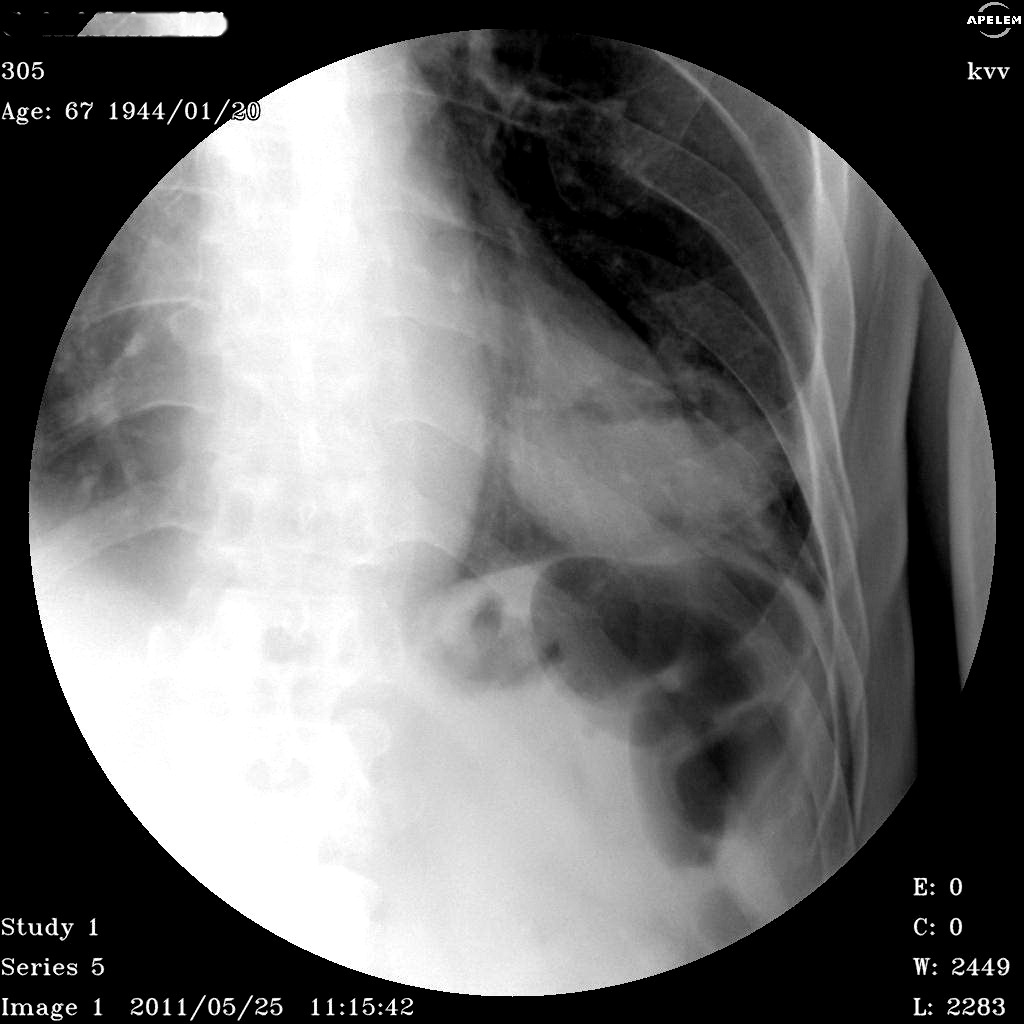

Коллега, прекрасное качество снимков (нижняя серия), на каком аппарате выпонены эти шедевры?

Спасибо за отзыв : аппарат русско-французко-итальянский Спектр АП. Телеуправляемый. Качество скопии плохое, а вот снимочки и томограммы не плохие.. вот только поле круглое и всего 30 см, готовлю обзор по аппарату думаю к июлю-августу выставлю на сайте